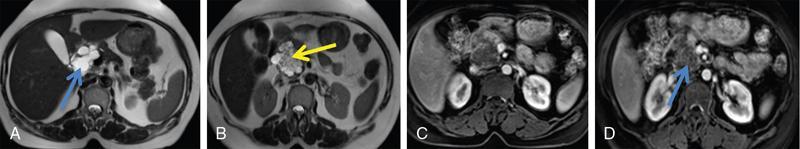

Ritu K. Kashikar, Shrinivas B. Desai, Pooja Punjani Vyas, Nilesh Doctor, Vivek Shetty Advancement and extensive use of imaging in recent times has to lead to increased detection and recognition of cystic pancreatic masses. Imaging however, plays a vital role in noninvasive diagnosis of these lesions, avoiding unnecessary intervention and planning management and follow up guidelines. The aetiology of pancreatic cysts ranges from primary cystic neoplasm to cystic degeneration of solid neoplasm to nonneoplastic cysts (Table 9.19.1). Cystic tumours of the pancreas comprise around 10%–15% of cystic lesions of the pancreas. The aim of this chapter is to educate the reader regarding imaging features of cystic lesions of pancreas, how to differentiate between cysts which can be left alone and those that require further management and also emphasize on latest international guidelines used in stratification of these lesions. Cystic pancreatic lesions are often incidentally detected on USG abdomen performed for other reasons. Although USG is an excellent modality for evaluation of cystic lesions elsewhere, it is unable to adequately characterize pancreatic cysts due to retroperitoneal location of the organ and other confounding factors such as obesity and gases. Most lesions detected on USG require characterization with either MDCT or MRI with MRCP. CEUS improves accuracy in the differentiation between a solid and a cystic lesion and also in determining whether enhancing septa or nodules are present within the cystic lesion. Currently USG also does not have a role in follow up algorithms of pancreatic cystic lesions. Multidetector CT evaluation of pancreatic lesions is best performed with a multiphasic technique (Table 9.19.2). The phases include a precontrast scan, an early arterial angiographic phase, a pancreatic parenchymal phase, and a portal venous phase. The precontrast scan is important for detection of calcification, which may be diagnostic of some lesions. Mucinous cystic neoplasms may be hyperdense on nonenhanced scan suggesting mucin content or haemorrhage. The arterial phase aids in detection of hyperenhancement neovascularity and arterial involvement in pancreatic masses. Optimal parenchymal enhancement of the pancreas is achieved at 35–45 seconds after initiation of injection of contrast agent. This is the pancreatic parenchymal phase. It is in this phase that the tumour pancreas contrast is maximum (Fig. 9.19.1, Table 9.19.3). Most hypoenhancing pancreatic lesions are best detected in this phase. The portal venous phase allows in detection of venous involvement and hepatic metastasis. Delayed phase is typically not required in cystic masses. MDCT has an accuracy of 56%–85% for characterization of cystic pancreatic lesions. MR imaging affords the best noninvasive means for the evaluation of cystic lesions of the pancreas due to superior soft tissue resolution. The helpful distinguishing characteristics of cystic pancreatic lesions, morphology of septae, relation to pancreatic duct are easier to detect at MR imaging and MR cholangiopancreatography (MRCP) than at CT (Table 9.19.4). Studies however indicate that MDCT and MRI are comparable in identifying malignant behaviour of cystic pancreatic lesions. The MRI protocol for evaluation of cystic lesions of pancreas includes T2-weighted single-shot fast spin-echo, T1-weighted in-phase and opposed-phase gradient echo, diffusion-weighted imaging, T2-weighted fat-suppressed fast spin-echo. Three-dimensional T1-weighted fat-suppressed spoiled gradient-echo T2-weighted MRCP. Postcontrast protocol includes dynamic three-dimensional T1-weighted fat-suppressed spoiled gradient-echo (in arterial, pancreatic and portal venous phases) (Fig. 9.19.2, Table 9.19.3). DWI has not found much utility in cystic neoplasms owing to overlap in ADC values. Some studies suggest role in distinguishing malignant from benign tumours in the case of mucinous cystadenoma and IPMN. Secretin is a peptide hormone produced in the intestinal mucosa, which stimulates the secretion of bicarbonate-rich fluid into the pancreatic ducts and transiently increases the tone of the sphincter of Oddi. The increased fluid distention of the pancreatic duct allows better study of ductal anatomy and identifying communication of pancreatic cystic lesions with the pancreatic duct. EUS is excellent in characterization of cystic lesions of pancreas. The proximity between the transducer and the lesions allows precise definition of the structural component of the cysts and components such as small mural nodules are better visualized with EUS than with other modalities. The other advantage of EUS is that cysts fluid aspiration and cytology can be performed. Tumour markers, genetic markers can be evaluated in the aspirated fluid. This allows comprehensive evaluation of cystic lesion. EUS also has therapeutic advantages allowing endoscopic draining of pseudocysts. Recently endoscopic ablation of cysts has been performed. These advantages have led to increasing use of EUS in recent years. This modality is however not indicated in all lesions and imaging should be able to stratify lesions requiring further invasive investigations. Studies have found PET CT comparable to PET alone or CT to determine presence of malignancy in cystic lesions. False positive findings may however be problematic. There is however no consensus for routinely using PET CT in characterization of cystic pancreatic masses. Serum CA19-9 and CEA are routinely done in all pancreatic masses. Though role in cystic lesions is still controversial. Serous cystadenoma is a benign neoplasm composed of glycogen-rich epithelial cells that form innumerable small thin-walled cysts containing serous fluid. It is the prototype microcystic pancreatic neoplasm. They occur frequently in older women (median age, 65 years) and is also called as grandmother lesion. Approximately 40% of pancreatic serous cystadenoma arise from the pancreatic head and uncinate process and 60% arise from the pancreatic body and tail. Serous cystadenomas are usually discovered incidentally at imaging; however, those that are large may cause symptoms. Patients may present with abdominal pain, palpable mass, anorexia, fatigue/malaise, or weight loss. Rarely the patient may present with jaundice. Genetic alterations similar to those in VHL are seen in sporadic SCA and include tumour suppressor gene VHL mutations and overexpression of vascular endothelial growth factor (VEGF). Allelic loss in chromosome 3 have seen in up to 40% cases of sporadic SCA. Serous cystadenomas are variable in size. The size ranges from <0.1 to 25 cm. The tumours are grossly well demarcated from the surrounding parenchyma. The gross appearance of the lesions is variable. It could be microcystic, consisting of innumerable small cysts giving the macroscopic appearance of a sponge or honeycomb. The presence of multiple, microscopic SCN is characteristic of von Hippel–Lindau (VHL). This variety show a centrally located area of fibrotic scar. In Macrocystic/oligocystic variant, borders with the surrounding parenchyma are less defined and the cystic lesion generally does not exhibit a central scar. The Solid variant, the lack of cystic spaces on gross inspection often gives the initial impression of a neuroendocrine or solid pseudopapillary neoplasm. Serous cystadenomas show nonviscous, clear-to-yellow cyst fluid, which provides an important clue to the distinction of SN from mucinous neoplasms. In contrast to intraductal papillary mucinous neoplasm, there is no connection with main or branch pancreatic ducts. These are clinically benign pancreatic epithelial neoplasms exhibiting serous morphology, characterized by a monotonous, cuboidal epithelial cell proliferation with marked cytoplasmic clearing due to intracellular glycogen. The centrally located epithelial cell nuclei are uniformly round to ovoid and not particularly large or hyperchromatic. Abundant diastase-sensitive cytoplasmic glycogen is highlighted by a periodic acid–Schiff stain. These lesions do not show evidence of necrosis, infiltrative architecture, or lymphovascular/perineural invasion, and mitotic figures are generally not observed. A variably prominent pseudocapsule of fibrosis divides parenchyma from the neoplasm On USG the microcystic variant shows lobulated contour with multiple tiny anechoic cysts separated by septae. the central scar containing calcification can be seen if present. Extremely microcystic, honeycomb variant may resemble a solid lesion at conventional US. The macrocystic type, can be mixed type with multiple large (>20 mm) and small cysts, and the unilocular type, which is more difficult to differentiate from mucinous cystadenoma (MCA). Enhancement of the intralesional sepatations is seen on contrast-enhanced USG allowing better characterization of the lesion. The central scar can show homogenous enhancement. Honeycomb variety appears as a hypervascular lesion owing to its extremely microcystic morphology and may resemble solid masses like neuroendocrine tumours. Pancreatic serous cystadenoma can have a varied appearance on CT depending on the morphologic patterns. Serous cystadenomas are typically solitary but may be multiple in von Hippel–Lindau disease, causing an appearance of disseminated involvement (Table 9.19.5). As mentioned previously, the polycystic pattern is the most common appearance of serous cystadenoma. A pattern of a bosselated collection of cysts that usually number more than six is seen. Each cyst may range from a few millimetres to 2 cm in size (Fig. 9.19.5). The other classic CT features include a lobulated contour and presence of a central stellate scar with calcification. This scar is seen in 30% cases and when present is strongly suggestive of the diagnosis. The intralesional fibrous septae show early enhancement after contrast administration. This is a distinguishing feature, as serous cystadenoma is the only hypervascular lesion among the cystic pancreatic neoplasms. Tiny cysts mimicking a honeycomb are the hallmark of this variant and may be poorly depicted as individual cysts on CT. On unenhanced CT, the honeycomb pattern may appear as a well-marginated lesion with soft tissue or mixed attenuation, depending on the size of the cysts and the amount of fibrous tissue. Moderate to strong enhancement is seen in these lesions (Fig. 9.19.6). This appears as a unilocular cyst or it may contain fewer large (>2 cm) cysts. Imaging Features include a lobulated contour, lack of a prominent thickened peripheral wall, and location in the head of the pancreas (Fig. 9.19.7). Owing to its supreme soft tissue resolution, MRI is the modality of choice in diagnosis of serous cystadenomas. The classic MRI features of microcystic variant includes a lobulated lesion with multiple small T2 hyperintense and T1 hypointense cysts with intervening hypointense fibrous sepate. These lesions do not communicate with the pancreatic duct; hence no dilatation is usually seen. Dilatation of pancreatic duct has however been reported in larger lesions. After the administration of gadolinium, the hypervascularization of the central scar and of internal septa may be seen. The morphology of the honeycomb pattern may also be better depicted on MRI. Multiple tiny T2 hyperintense cysts with intervening hypointense septae are seen (Fig. 9.19.8). The oligocystic variant shows fewer larger T2 hyperintense and T1 hypointense cysts and can mimic mucinous cystadenoma. However, the lobulated contour, together with the absence of wall enhancement and a wall thickness less than 2 mm, suggest the correct diagnosis (Fig. 9.19.9) (Table 9.19.6). The differential diagnosis of serous cystadenoma depends on the variety and are listed in Tables 9.19.7 and 9.19.8. Lesions with classic imaging features do not require further investigation or fluid analysis. The fluid in classic cystadenomas is yellow in colour and does not show elevated amylase, mucin or tumour markers. Approximately 20%–50% cases show cytological positivity for periodic acid-Schiff and cytokeratin AE1 and 3. Hemosiderin laden macrophages also do not have high diagnostic accuracy and are seen in only about 43% cases. Current management guidelines suggest (Table 9.19.9). Resection involves distal pancreatectomy or Whipples, depending on location of the tumours and is currently reserved for truly symptomatic cases. Mucinous cystic tumours are a rare subset of cystic neoplasms, constituting approximately 2.5% of pancreatic exocrine tumours. TABLE 9.19.10 The defining and characteristic histopathologic feature of mucinous cystic neoplasms (MCNs) is the presence of ovarian-type stroma similar to that observed in biliary cystadenomas. International Association of Pancreatology recommend that all suspected MCNs be surgically resected. A significant female predilection is seen with approximately 99.7% cases seen in women. As opposed to serous cystadenomas these lesions occur in middle aged women and hence the term mother lesions is used to describe these. The approximate age of occurrence is 50 years with a range from 20–82 years. Mucinous cystic tumours are a dominant cyst that is round or oval and is encapsulated. MCNs may grow slowly over time, at an average rate of 4 mm per year. The most common locations are the pancreatic body and tail (up to 75%). Stromal elements similar to ovarian stroma are the hallmark and key feature that aids in differentiation from IPMN, whose stromal elements are ductal in origin. Tall columnar cells with intracellular mucin arranged in a single row or vertically, forming papillary or polypoidal projections, constitute the epithelial elements. Portions of benign appearing epithelium can be seen adjacent to areas of invasive carcinoma in the same tumour. These lesions show smooth contour on gross appearance with few internal sepate. Peripheral calcification, mural nodule if present suggest malignant cyst (Fig. 9.19.11, Table 9.19.11). Lesions may be asymptomatic in 25% cases. Patients my present with pain in abdomen. Mucinous cystadenoma can also present with pancreatitis. Considering most lesions are located in distal body and tail involvement of splenic vein may lead to left sided portal hypertension. Mucinous cystic tumour is a well-circumscribed cystic mass in the pancreas. Lesions can have an irregular contour to the wall, septations, mural nodularity, and peripheral calcifications. The lesion may however be echogenic due to high by mucin content or haemorrhage which may impair the detection of other features. CEUS may improve detection rate of septa and mural nodules. Lesions are typically well-circumscribed with smooth contour. On unenhanced CT, mucinous cystadenoma may appear hypodense or slightly hyperdense content, due to the presence of variable amount of mucin and haemorrhage. Curvilinear calcifications occur along the periphery of the lesion and are seen in 15% of cases, in contrast study enhancement of the fibrous cyst wall along with enhancement of any septations or mural nodules is seen (Figs. 9.19.12 and 9.19.13).